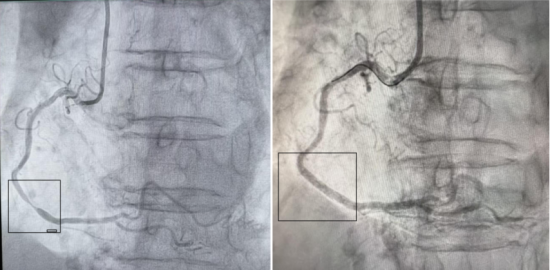

检查结果证实了专家的预判,冠脉CT显示,患者左冠状动脉和右冠脉存在严重的重度狭窄,这意味着李女士不仅面临脑卒中风险,更随时可能突发急性心肌梗死的危险。病情就是命令,神经内科专家迅速启动泛血管疾病管理中心多学科会诊(MDT)机制,心内科专家紧急介入。面对心、脑两处极高危病变,医生们犯了难。经过MDT团队深入评估,一致认为:冠状动脉病变是当前对生命最直接、最迫切的威胁。团队果断决策,“先心脏,后颈动脉”,优先为李女士实施冠状动脉支架植入术,稳住了生命中枢。

冠脉造影:右冠脉重度狭窄 右冠脉支架术后

然而,新的挑战接踵而至。因李女士体重较轻,肌酐略有增高,若同时接受两次需要使用造影剂的大型介入手术,将面临较高的肾损伤风险。一切以患者安全为中心,团队再次展现了精细化、个体化管理的水平。他们没有追求速度,而是科学地将颈动脉支架手术安排在心脏手术两天后进行,给予身体充分的代谢恢复时间。两天后,第二颗“炸弹”也被成功拆除。手术过程平稳,患者未出现任何并发症。